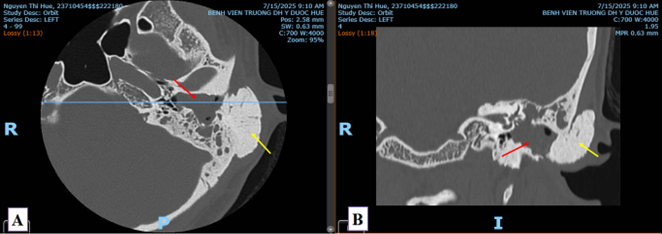

Hình 3: Phần tổn thương ung thư xâm lấn gần như toàn bộ chu vi xương chày về mặt cắt ngang, nhưng chưa xâm lấn bó mạch chày trước (phần khoanh tròn đỏ)